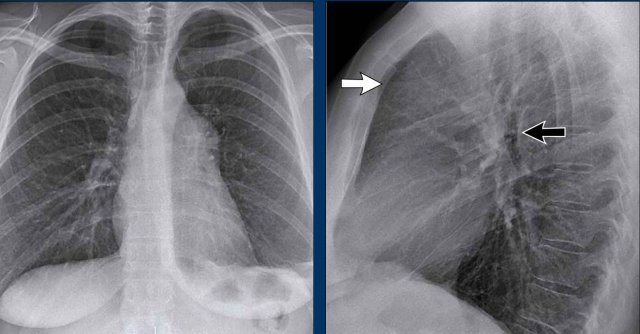

Displacement of the Azygoesophageal Line (1) – Hiatal hernia

A hiatal hernia (arrowheads) is the most common cause of displacement of the azygoesophageal line as seen on the PA-view.

Notice the air within the hernia on the lateral view (black arrow).

Displacement of the Azygoesophageal Line (2) – Subcarinal Lymphadenopathy

A common cause of displacement of the azygoesophageal line is subcarinal lymphadenopathy (station 7).

On the chest X-ray, note superior displacement of the azygoesophageal line just below the carina, consistent with enlarged subcarinal lymph nodes (black arrow).

Additional right paratracheal lymphadenopathy is seen, displacing the right paratracheal stripe (white arrow) and deviating the trachea to the left.